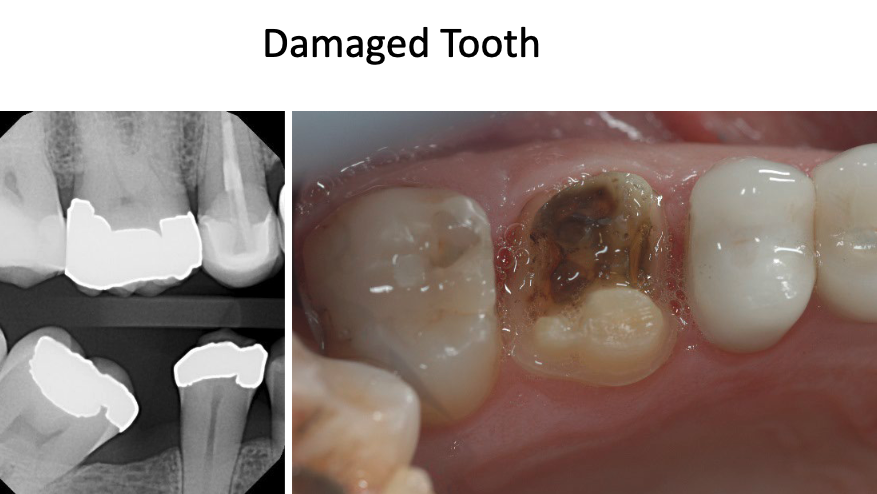

what restoration would we do on this MOD fractured tooth?

single crown (full coverage)

what treatment should be done for this tooth?

indirect restoration like crown